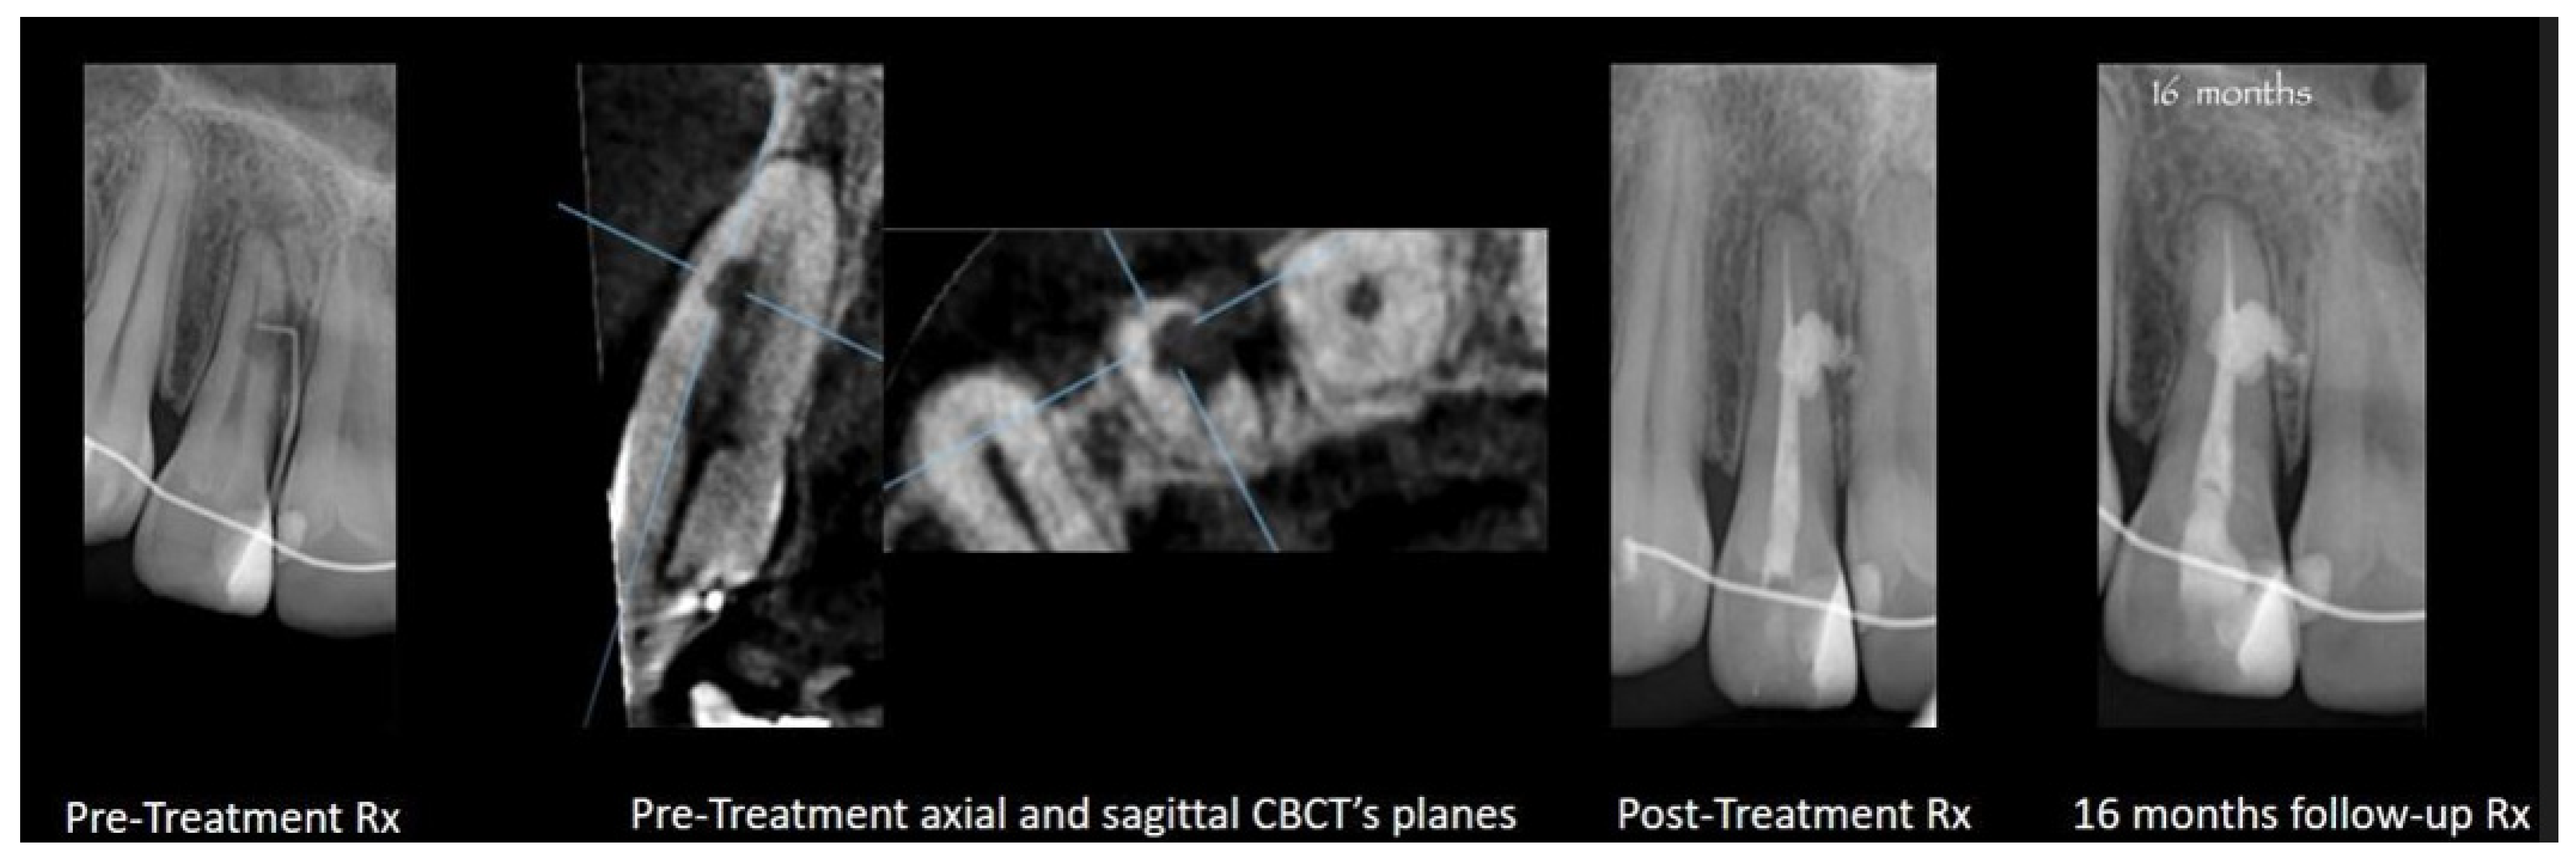

2.3. Root Canal Treatment for Teeth in Close Proximity to Anatomic Structures

2.6. Iatrogenic Aberrations